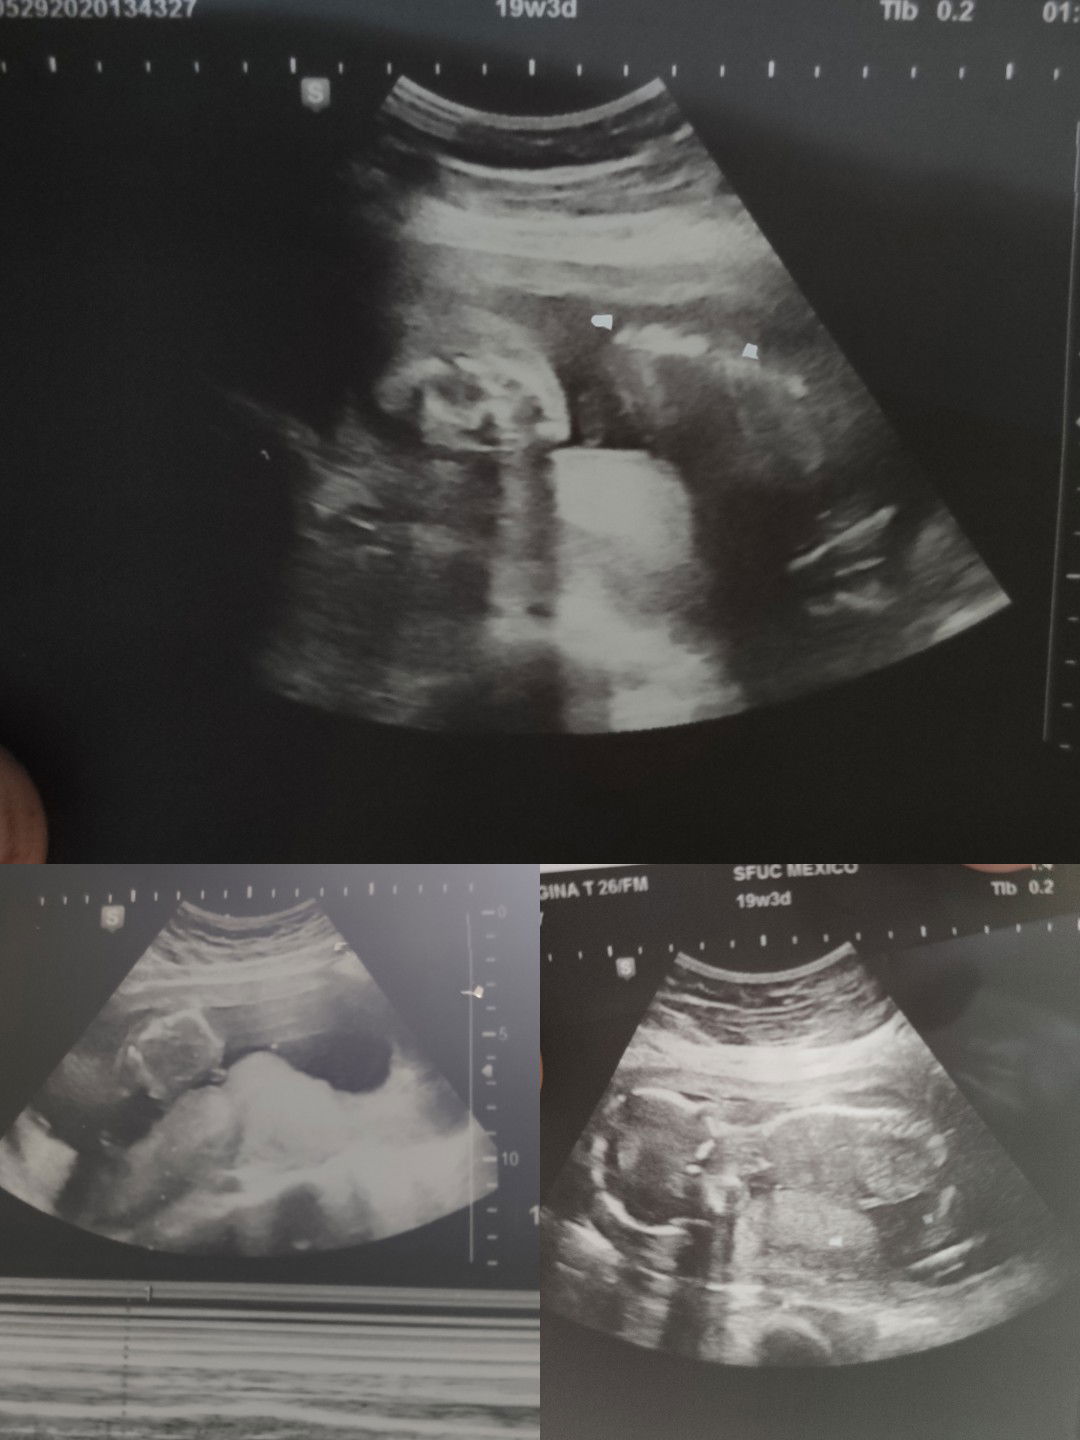

mom to be ❤️

may gender nabang makikita dito?

Good eve po mamsh.. hindi ko po magets ung mga picture sa ultrasound? kung mukha ba or what. Isa lang po ung medyo nagegets ko posisyon ung nakapadapa ung baby.. ung isa na parang pwet di ko magets kung ano pero may kahit 60/40 chance na po ba ng gender n makikita.. ? thanks po